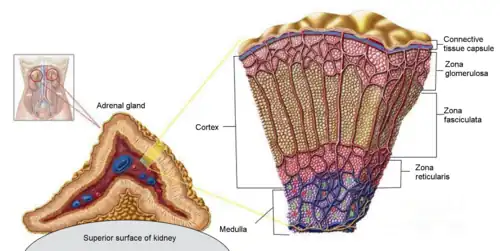

Adrenal Glands

Adrenal glands, also known as the suprarenal glands, are located above each kidney and in the retroperitoneal space. They produce and regulate different hormones, including stress hormones like cortisol and hormones that regulate salt and water balance like aldosterone.[3] The glands are triangular-shaped and are composed of two types of tissues: the cortex and the medulla. The glands are surrounded by a capsule made up of connective tissue[4] and consist of outer portion or the cortex, and the inner portion or the medulla. The outer cortex is further divided into three layers, named the zona glomerulosa, zona fasciculata and zona reticularis, all which produce critical steroid hormones.

The inner portion or the medulla produces catecholamines such as adrenaline (epinephrine) and norepinephrine. Mineralocorticoid hormones like aldosterone, which regulates blood pressure, kidney function, and certain sex hormones, are produced by the outer layer of the adrenal cortex or the zona glomerulosa.Glucocorticoids, which are produced by the middle layer of the adrenal cortex, or the zona fasciculata.[4] Glucocorticoids are critical for regulation of blood sugar and the immune system, as well as response to physiological stress. Androgens, which aid in the development of secondary sex characteristics, are produced by the inner zona reticularis. DHEA (dehydroepiandrosterone) is the most commonly found hormone in the body and is a precursor in the production of progesterone, estrogen, cortisol and testosterone.[4]